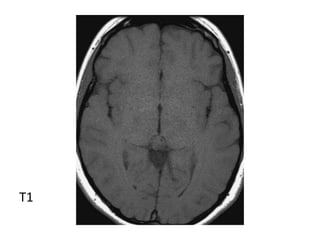

*T1 :

-Typically iso to low signal compared to brain

parenchyma